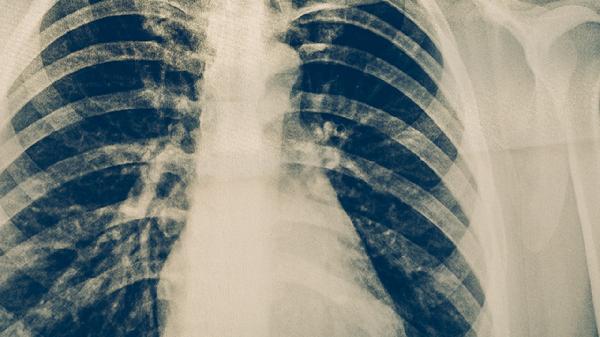

肺结核是传染病。肺结核是由结核分枝杆菌引起的慢性传染病,主要通过呼吸道飞沫传播。

肺结核主要通过呼吸道飞沫传播。当活动性肺结核患者咳嗽、打喷嚏或大声说话时,会将含有结核菌的微小飞沫释放到空气中。健康人吸入这些飞沫后,结核菌可能进入肺部并引起感染。感染后是否发病取决于人体免疫力的强弱。免疫力较强的人可能仅形成潜伏感染而不发病,但免疫力低下时,结核菌会大量繁殖导致活动性肺结核。预防肺结核传播的关键措施包括及时发现和治疗患者,保持室内通风良好,以及在高风险环境中佩戴防护口罩。

部分肺结核患者可能不具有传染性。并非所有肺结核患者都会传播疾病,传染性主要取决于患者肺部病灶的性质以及痰液中是否含有结核菌。只有痰涂片或培养阳性的活动性肺结核患者才具有传染性。一些肺结核类型,如结核性胸膜炎或肺外结核,通常不具有传染性。经过规范抗结核治疗数周后,患者的传染性会显著降低甚至消失。对于确诊的患者,遵循医嘱完成全程治疗是控制病情和消除传染性的根本方法。